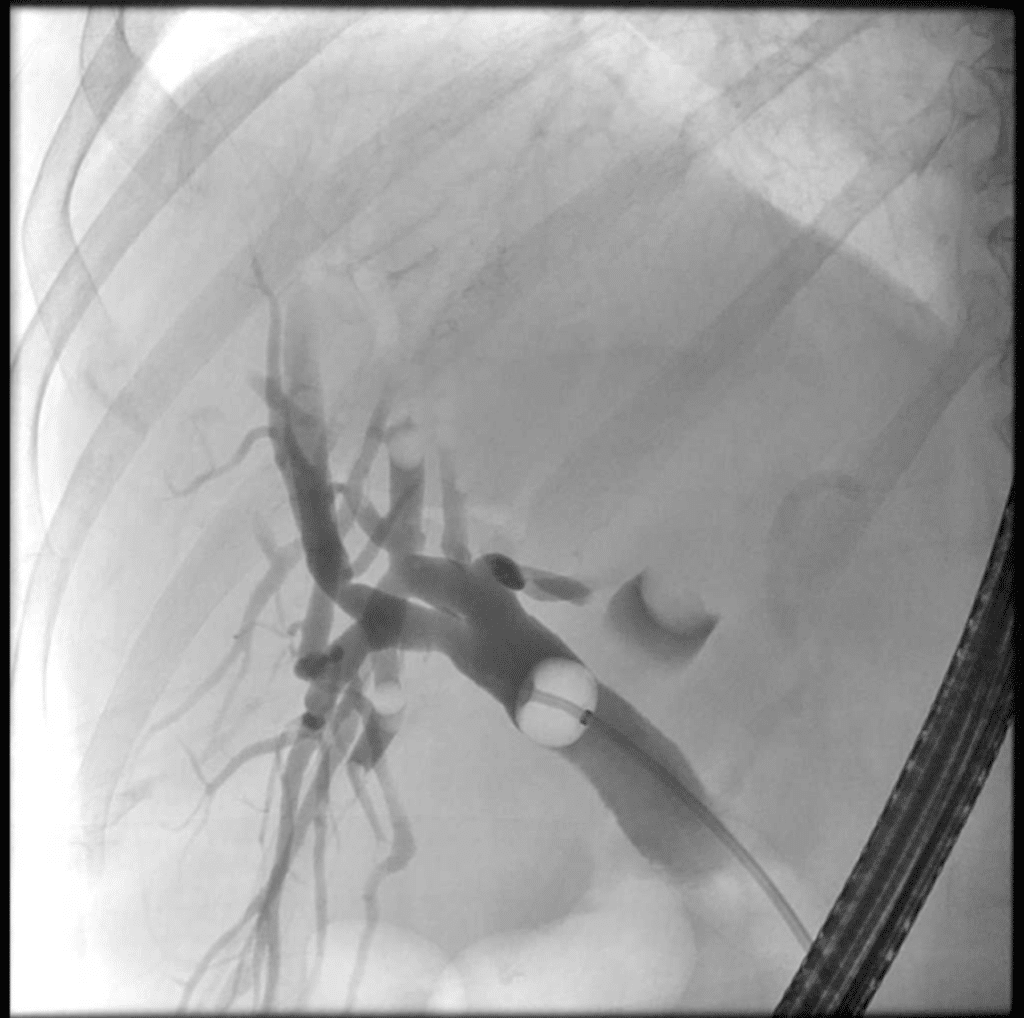

77-jährige Patientin mit Cholangitis bei ausgeprägter Choledocholithiasis und unklarer hilärer Stenose. Die Zuweisung erfolgte aus einem auswärtigen Haus, der V. a. ein perihiliäres cholangiozelluläres Karzinom wurde geäußert. Eine Papillotomie mit Extraktion von Konkrementen aus dem DHC erfolgte bereits. Zur genauen Darstellung der Stenose des Hilus führten wir einen Ballon in den Gallengang und füllten oberhalb mit Kontrastmittel: das rechte Gallenwegssystem erschien dabei unauffällig, links stellte sich eine große Kontrastmittel-Aussparung dar. Wir sondierten die Region mit Cholangioskop, hier zeigte sich ein großes Konkrement. Durch elektrohydraulische Lithotripsie (EHL) gelang die Zertrümmerung, mithilfe des Füllungsballons konnten multiple Konkremente entfernt werden. Eine tumoröse Stenose zeigte sich nicht. Sonographisch sahen wir am Folgetag Aerobilie.